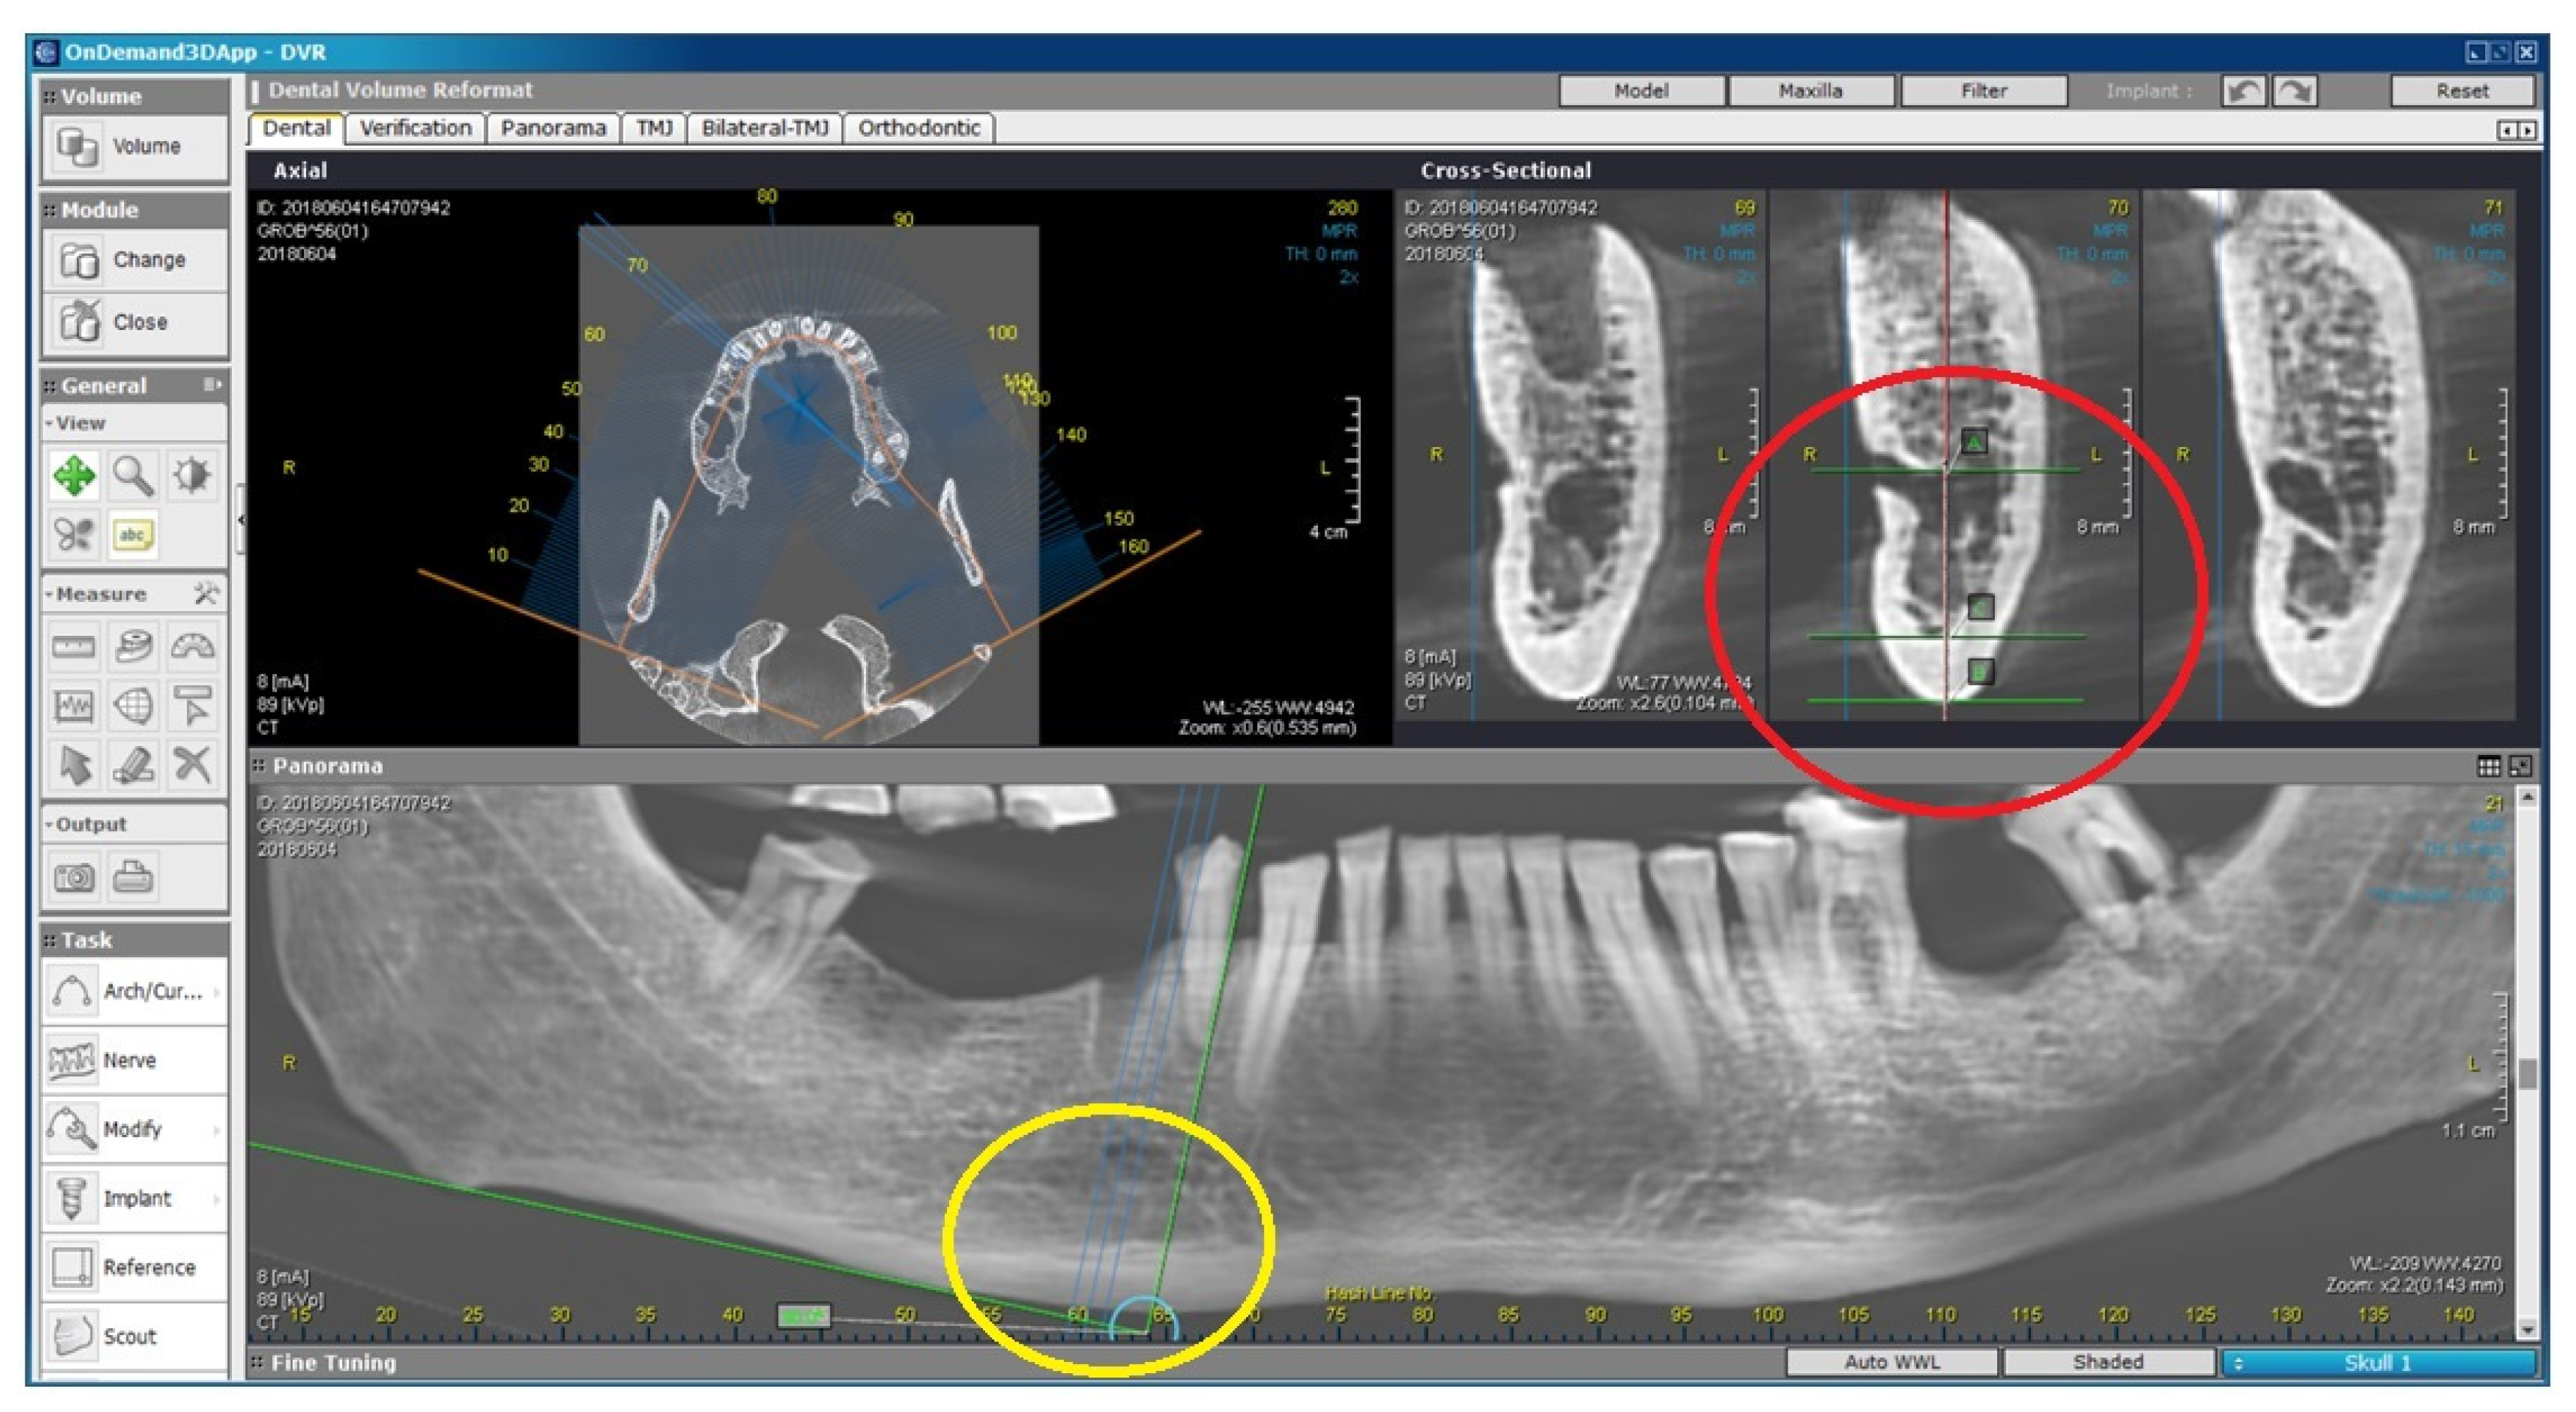

2.2. Radiomorphometric Assessments